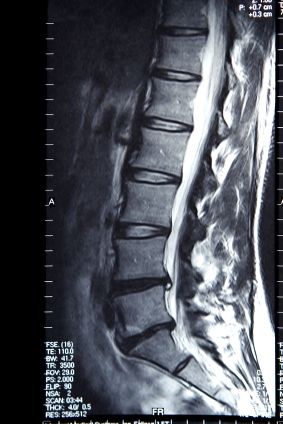

МРТ поясничного с красителем

МРТ поясничного с красителем фото

МРТ является магнитно-резонансная томография, специальный тест визуализации, которая не использует рентгеновских лучей. МРТ в нижней части спины можно определить связок, мышц, нервов, диски, кости и спинной мозг. Это самый лучший тест для обнаружения артрит, грыжа межпозвоночного диска, спинного инфекции, повреждение спинного мозга, повреждения нерва, и рак спины и спинного мозга. Краситель имени гадолиния используется, которые могут предоставить дополнительную информацию. Гадолиния иногда используется, чтобы определить разницу между воспаления, травмы или рак.